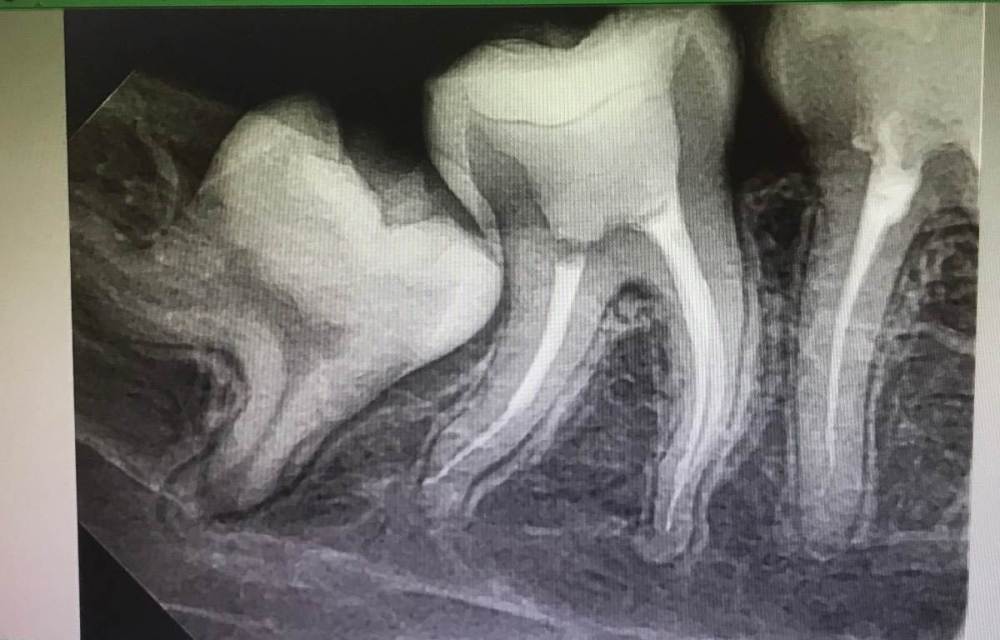

cryptiik Опубликовано 5 февраля, 2023 Поделиться Опубликовано 5 февраля, 2023 (изменено) Доброго времени суток! Столкнулась с такой проблемой — болит зуб 4.7 после лечения и пломбировки каналов. Лечение проводилось как полагается: два раза ходила с лекарством закрытым временной пломбой, затем наконец произвелась чистка каналов и их пломбировка. Длилось это мероприятие долго ввиду того, что корни у меня сильно искривлены. Больно не было, скорее неприятно от того, что ощущала инструменты внутри. Спустя часа 4 с того момента, как поставили постоянную пломбу и я начала отходить от анестезии, начались боли. Это естественная реакция организма. Я это понимала, так как зубы лечу часто. Боль была очень сильной, особенно в ночное время, даже просыпалась от этого. Обезболивающие помогали плохо. На второй день зубная боль начала отдавать в голову и в ухо. На третий день было полегче, но все также болело и пульсировало время от времени. Сейчас идёт 5-й день, на зуб больно надавить, ощущается ноющая и иногда пульсирующая боль. Забыла сказать, что снимок этого зуба сделала на второй день после лечения. Отправила доктору, он сказал, что все хорошо. Но у меня вызывает опасения такая боль. Нормально ли это? И насколько хорошо мне запломбировали каналы? Снимок прилагаю. Изменено 5 февраля, 2023 пользователем cryptiik Ссылка на комментарий

Carioznik Опубликовано 5 февраля, 2023 Поделиться Опубликовано 5 февраля, 2023 Если смотреть по снимку, то лечение проведено хорошее, так сильно, как Вы описываете, по идее, зуб болеть не должен. Предположу , что причина в другом зубе, скорее всего, в каком-то из верхних справа 1 Ссылка на комментарий

cryptiik Опубликовано 5 февраля, 2023 Автор Поделиться Опубликовано 5 февраля, 2023 @Carioznik то есть тот больной зуб может отдавать в пролеченный или как? плохо понимаю, как это связано, и что можно с этим сделать. плюс смущает один из каналов, который будто бы не до конца запломбирован (на снимке пустота?), но я в этом некомпетентна. можете проконсультировать относительно этого момента, пожалуйста? Ссылка на комментарий

Carioznik Опубликовано 5 февраля, 2023 Поделиться Опубликовано 5 февраля, 2023 7 минут назад, cryptiik сказал: то есть тот больной зуб может отдавать в пролеченный или как? Нет. В пролеченом у Вас могут быть терпимые ноющие боли и боли при накусывании. А сильные пульсирующие, ночные уже от другого зуба(скорее всего верхнего) 12 минут назад, cryptiik сказал: один из каналов, который будто бы не до конца Если смотреть на этот снимок, то все хорошо. Но идеале, сделать КТ Ссылка на комментарий

Carioznik Опубликовано 5 февраля, 2023 Поделиться Опубликовано 5 февраля, 2023 По КТ уже можно будет более точно проверить , может есть дополнительный канал в одном из корней леченного зуба. Ну и за одно проверить соседние и верхние на скрытые кариесы Ссылка на комментарий

Carioznik Опубликовано 8 февраля, 2023 Поделиться Опубликовано 8 февраля, 2023 05.02.2023 в 17:58, cryptiik сказал: у меня 4.6 со вторичным кариесом, может он и болит. сложно определить, так как обширная область ноет. Этот 46 зуб, если смотреть на ту его половину , что влезла на снимок, вряд-ли так может болеть. Несмотря на кариес Ссылка на комментарий